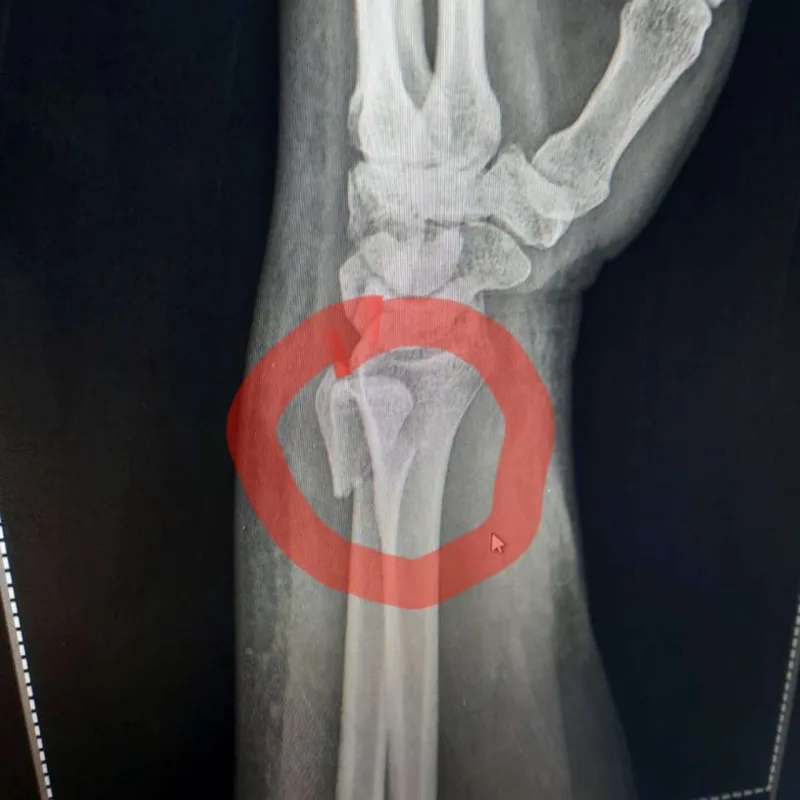

Tanınmış aparıcı Aytən Səfərovanın başına iş gəlib.

OLAY yazır ki, aparıcının bilək sümüyü sınıb. Bu barədə Səfərova instaqramda məlumat yayıb. O bildirib ki, bu günlərdə anası ağır əməliyyata hazırlaşır:

“Çox çalışdım ki, könlümü fərəh tutum, fikirləşdiyimi büruzə verməyim, özümü “sındırmayım”, lakin sümüyümü sındırdım. Həkimlər vaxtında müdaxilə etdilər.  Hələ ki, ağrıkəsicisiz mümkün deyil, amma biz güclü qadınıq. İnşallah bu da keçər. Özünüzü qoruyun”.

Aytən biləyini sındırdı - Fotolar Aytən biləyini sındırdı - Fotolar Aytən biləyini sındırdı - Fotolar Aytən biləyini sındırdı - Fotolar